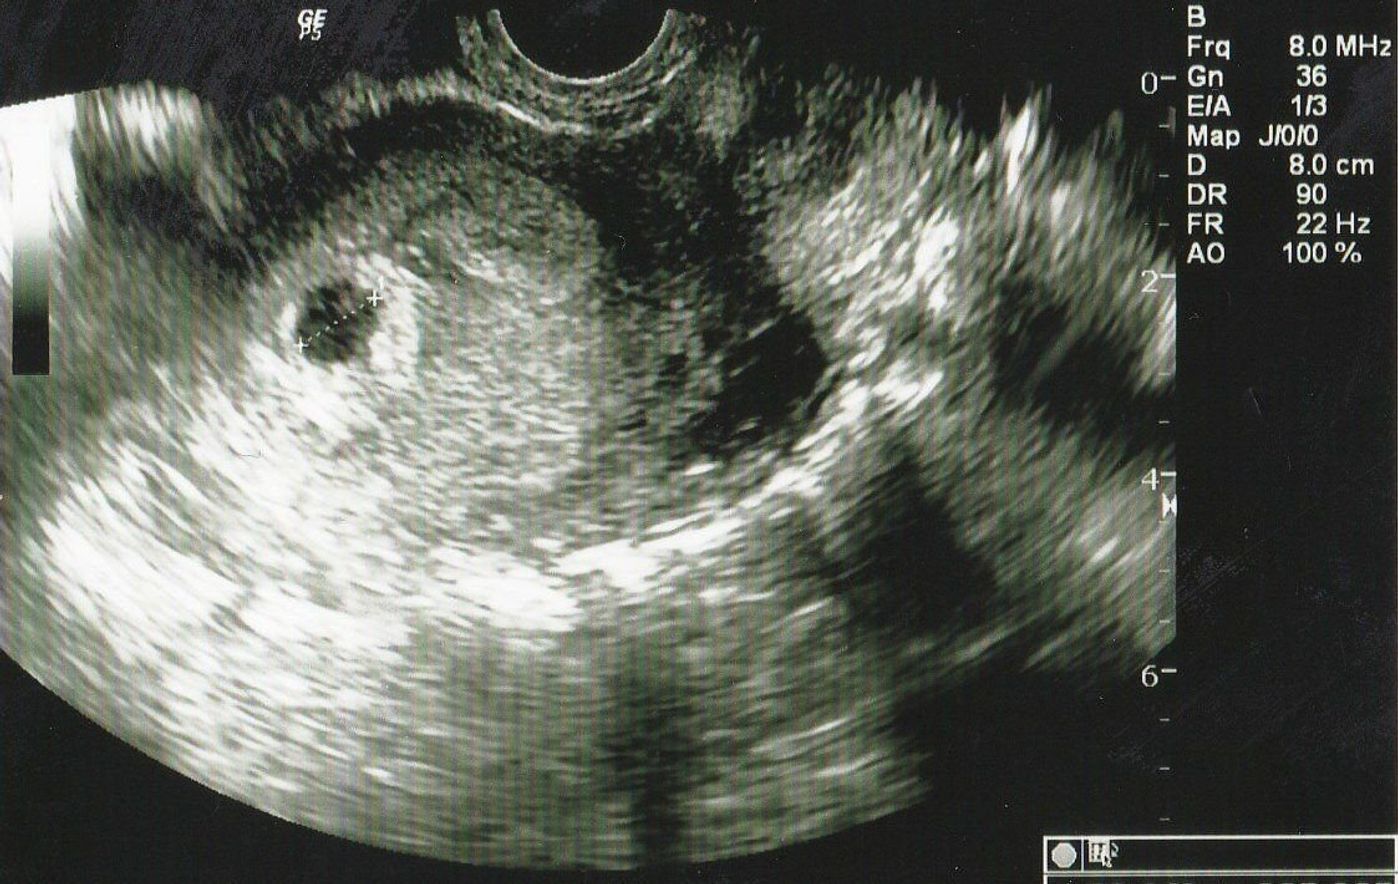

4週 エコー 胎嚢-胎嚢の大きさ(赤ちゃんが入っている袋の大きさ) 上記エコー写真ですと4週1日目ということになります。 妊娠4週目 受精卵が無事に着床して胎嚢が成長を始めています。胎嚢は赤ちゃんが入る袋のことで、早ければ妊娠4週のはじめに確認でき、一般的には 妊娠4週末から妊娠5週頃 までに見えます。 胎芽は妊娠6週頃に確認できたというケースが多く、心拍は早ければ妊娠5週のはじめ・妊娠8週までには全ての妊婦さんに見られ

子宮内に胎嚢が確認できるのは、早ければ、胎嚢が直径2mmくらいになる妊娠4週後半ごろから。 妊娠5週ごろまでは1日1mmのペースで大きくなっていき、6週ごろには確認できることが多いようです。 妊娠5週ごろの様子 胎嚢の大きさは1cm前後。 生理がこない、基礎体温が上がったままで妊娠に気づき始める 市販されている多くの妊娠検査薬の使用期間は、生理予定日の1週間後を推奨しているので、妊娠4週の最後の頃、5週目に入る頃には検査で陽性反応が出る可能性が高くなってきます。 この時期の赤ちゃんは「胎芽」と呼ばれる時期で、目では確認できない大きさです。 赤ちゃんを包む胎嚢という袋が 31 7週0日(胎嚢) (妊娠2ヶ月) 32 10週0日(赤ちゃん現れる) (妊娠3ヶ月) 33 12週0日(頭の形がわかる) (妊娠4ヶ月) 4 実際のエコー写真:妊娠中期 (妊娠5ヶ月~妊娠7ヶ月) 41 16週0日(3Dあり) (妊娠5ヶ月) 42 19週6日(各部位の測定開始

これがこの時もらったエコー写真です。子宮だけ写ってる。。 一般的には、4週後半から5週前半に胎嚢が確認でき、5週後半から6週前半で胎芽や心拍の確認ができる そうです。 となると、5週2日の私は胎嚢が確認できるはずだったのですが。 エコー写真では、GS (gestational sacの略)と表記されます。 一般的に、胎嚢は妊娠4週後半~5週頃にかけて確認することができるとされています。 通常は、胎嚢・胎芽・心拍の三つを確認できた時点で、正常妊娠であると診断されます。 ただし、胎嚢が確認8週4日のエコー写真で胎嚢の隅っこに赤ちゃんがいましたが同じような方いらっしゃいますか😢? 胎嚢も少し長く何が正常なのかわからないので不安です(;_;) 1月16日 お気に入り 妊娠8週目 赤ちゃん 胎嚢 エコー写真 みいぽん 酢 (3